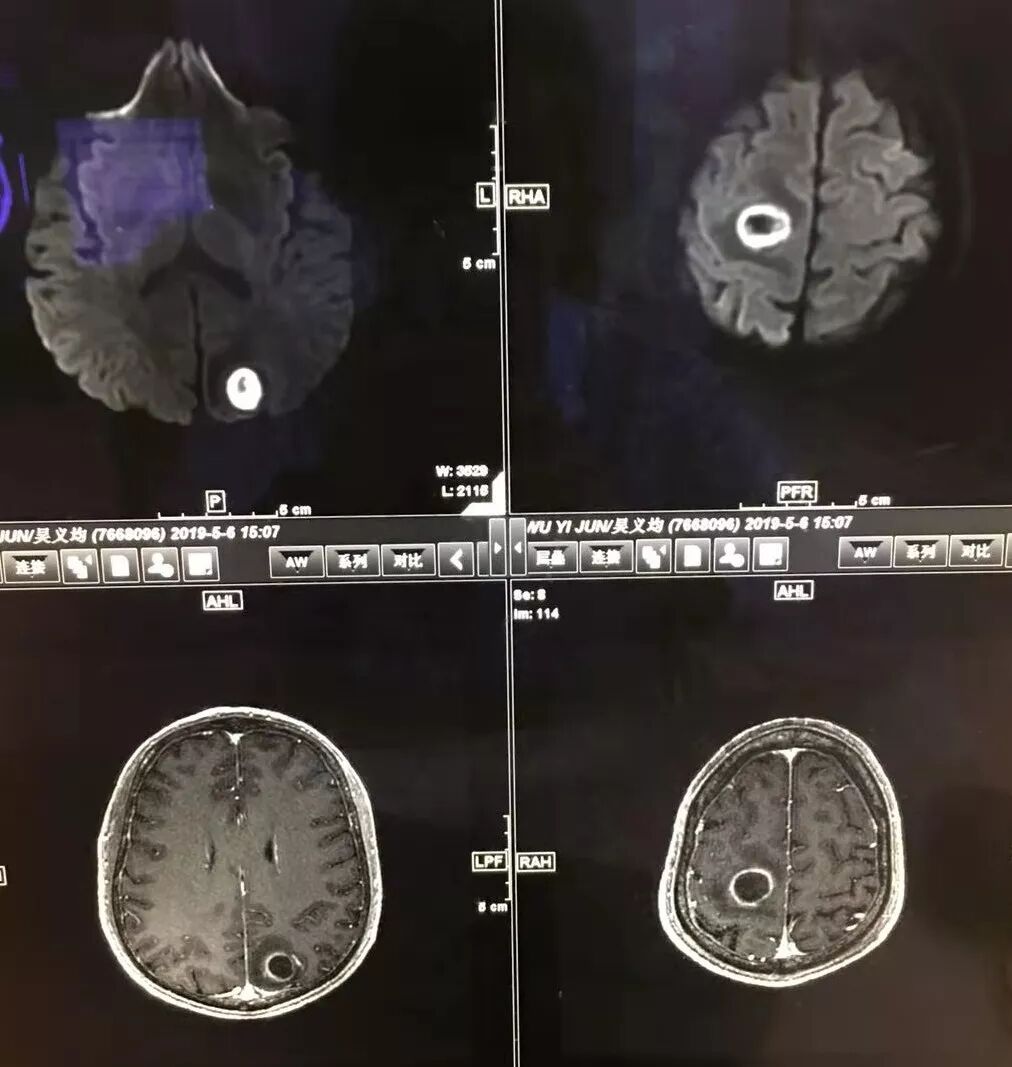

右肺下叶见不规则软组织影,边缘不清,内夹杂气体,背段支气管未见明显阻断,增强扫描下叶病灶内见类圆形低强化区,其边缘光滑,见低强化区壁,颅脑左侧枕叶及双侧顶叶见多发长T1长T2信号,T2高信号内见类圆形异常信号,壁呈低信号,DWI环形壁未弥散受限,内容物弥散受限,周围为水肿区,增强扫描呈多发环形强化,考虑血源型感染,颅内及右肺下叶脓肿形成

右侧顶叶这个病灶影像上更加支持转移,环形强化,弥散环形受限,外周水肿明显

转移瘤,环形强化的壁很多都弥散受限,脓肿是中间脓液也要受限

右顶叶这个弥散,强化,外周水肿都是典型的转移瘤表现

多数薄壁,脓腔弥散受限是典型脑脓肿;右侧额叶的厚壁,壁受限,表现跟其他完全不一样,很是疑惑

颅内部分病灶是环形受限,中心没有受限,不支持脓肿

今天这个颅脑病灶需要转移和脓肿鉴别,转移和脓肿都可以这样环形强化,但是脓肿是中心弥散受限,脓肿壁弥散不受限,转移和脓肿弥散正好相反,转移是环壁弥散受限,中心坏死区弥散不受限。

脑内多发结节,DWI壁弥散受限,腔不受限

强化内外壁部分区域稍毛糙

脑内病灶支持恶性

颅内环形的高信号,但是可以发现这个的DWI环是厚的,但是增强扫描的环是非常薄的,如果是肿瘤的,就是壁的弥散受限是肿瘤细胞的话,那么他强化的环应该跟DWI的环的厚度是一样的,所以这个环形的低DWI高信号应该是脓肿。而且就是关于这个脓腔壁的,就是脓腔的外壁是非常模糊的,而内壁还是相对光整,环不是很完整。下面一个图,没有给到,DWI上可以看到沿着破溃的脓肿壁向外侵出去的感觉,如果是环形转移的,那么它的那个内壁是更加不光整,而外壁是相对比较清楚一些的。

这个颅内病灶增强扫描的无强化区范围与DWI高信号范围是一致的,所以还是脓腔内受限,至少时期不那么典型,不是纯粹的高信号,DWI是厚层、增强是薄层;而且扫描角度也不一样,所以无法完全对上

3.脑内多发混杂信号病灶,显著长T1、显著长T2信号为主。注意TW1及TW2均显示环形等密度影(这在转移瘤是非常罕见的)且出现相应的环形强化。中央液化区DW扩散受限以及周边广泛水肿等,都符合典型多发脑脓肿改变。